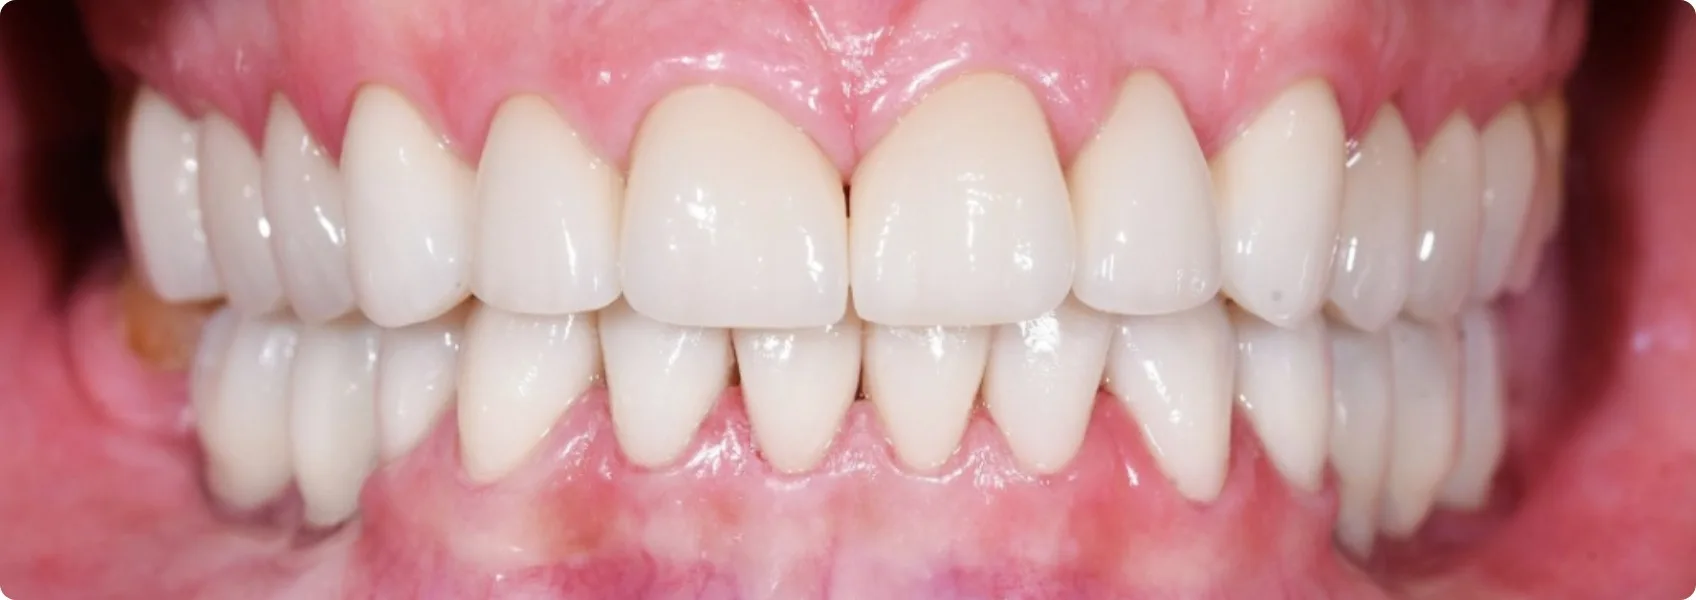

Finał: korony, implanty i most przywróciły uśmiech i komfort.

Gdy zgryz został prawidłowo ustawiony, a wszystkie zęby wyleczone i przygotowane, nadszedł czas na powrót do gabinetu protetycznego i finalną odbudowę.

Na przeleczonych, wzmocnionych zębach własnych Pacjenta doktor Adrian osadził estetyczne korony protetyczne. Po lewej stronie żuchwy wykonał dwie pojedyncze korony bezpośrednio na implantach. Po prawej — most protetyczny podtrzymywany przez dwa implanty. Łącznie pięć nowych zębów wypełniło luki.

Efekt? Ulga w bólu, nowy uśmiech, nowa jakość życia.

Wyleczyliśmy ból stawów. Przywróciliśmy funkcjonalność zgryzu, dzięki czemu Pacjent po raz pierwszy od lat mógł normalnie i bez bólu gryźć, żuć i mówić.

Poprawiliśmy nie tylko funkcję, ale i estetykę. Uśmiech stał się równy, bielszy, po prostu piękny! Pacjent odżył i odzyskał pewność siebie.

Taki wynik leczenia potwierdza skuteczność podejścia interdyscyplinarnego — wspólna praca protetyka, endodonty i chirurga pozwoliła przywrócić funkcjonalność całego układu stomatognatycznego na lata.